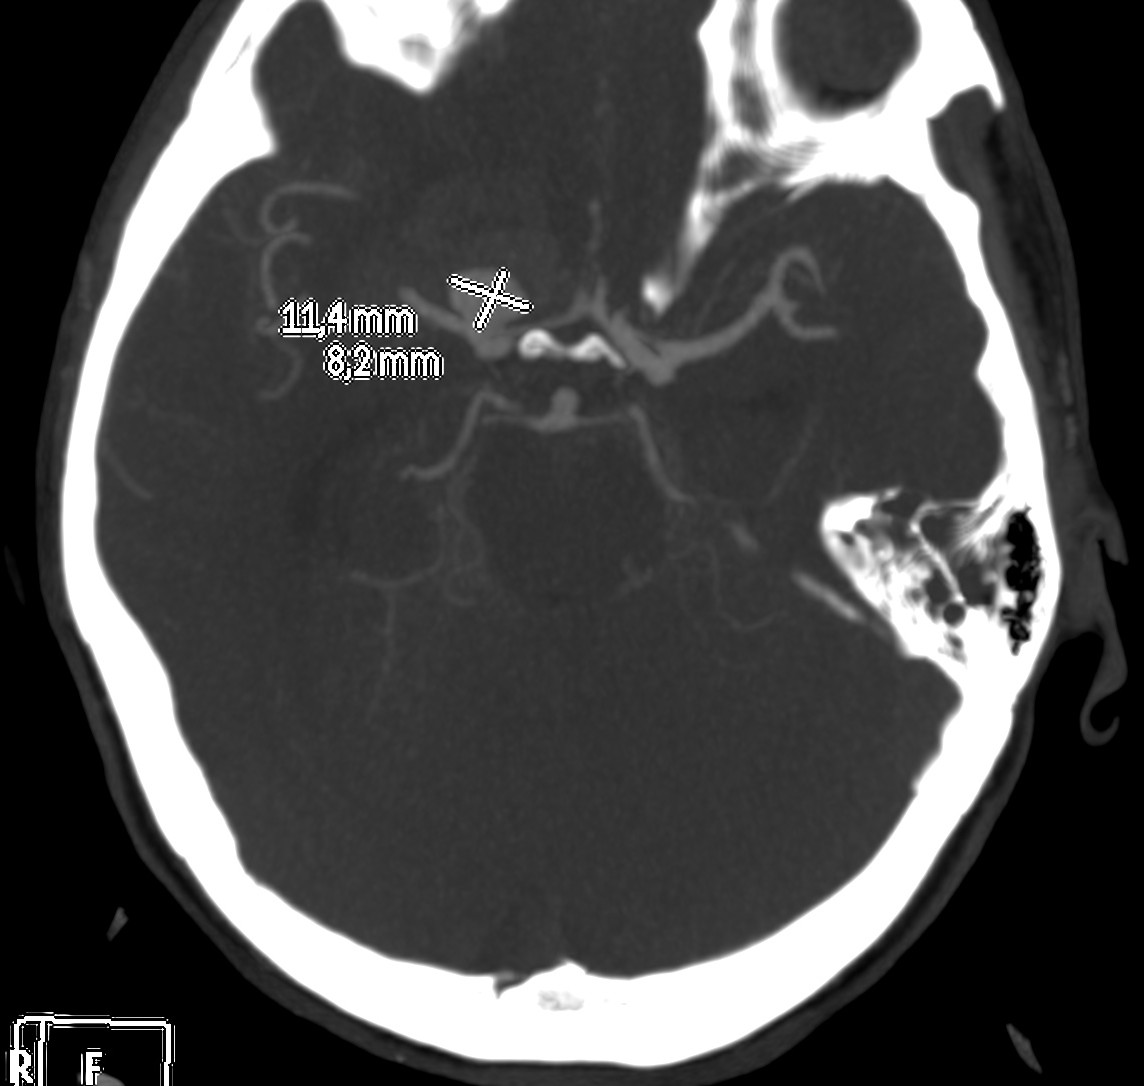

Se decide realizar Angio-TC.

Estamos ante una Hemorragia Subaracnoidea por rotura aneurismática.

El 85% de las hemorragias espontáneas en el espacio subaracnoideo son debidas a la ruptura de un aneurisma. Se deben a la evaginación de la íntima y la adventicia, la clave es la ausencia de lámina elástica interna y capa muscular. Se da en el 1% de la población y entre el 2-30% pueden ser múltiples. El 90% de los aneurismas cerebrales se localizan en la circulación anterior, los localizados en la ACM dan la típica imagen de hiperdensidad en las cisternas basares cuando se rompen.

Angiografía- TC: Se basa en la TC de cortes helicoidales. Aunque implica radiación para el paciente y requiere administración de contraste iodado intra-venoso (no requiere cateterización arterial), el hecho de que posea gran disponibilidad y sea una técnica rápida y fácil de llevar a cabo en pacientes enfermos, hace que se use como prueba de primera línea. Se puede realizar con cortes de 1 mm y realizaremos reconstrucciones para obtener imágenes como las de una angiografía (cine + MIP).